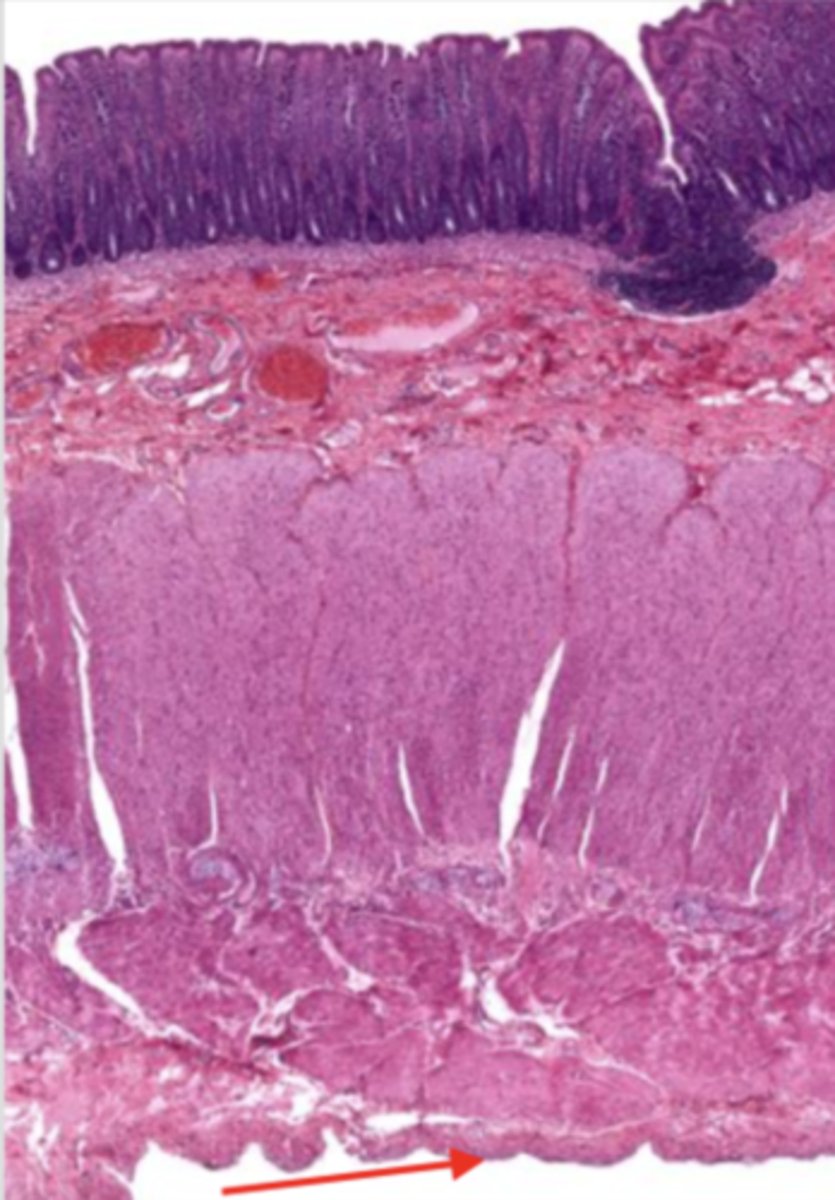

cardiac stomach (histology)

simple columnar epithelium

what kind of epithelium lines the mucosa of the cardiac stomach?

gastric pit (cardiac stomach)

lumen (cardiac stomach)

mucosa (cardiac stomach)

mucosal epithelium (cardiac stomach)

lamina propria (cardiac stomach)

muscularis mucosa (cardiac stomach)

submucosa (cardiac stomach)

contains glands and blood supply

muscularis externa (cardiac stomach)

serosa/adventitia (cardiac stomach)